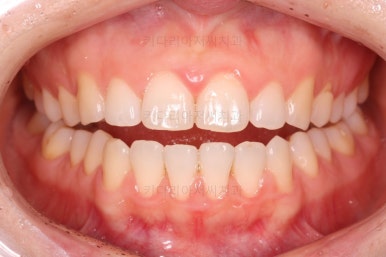

벌써 치료 종료시의 모습입니다.

치료는 총 5개월이 걸렸네요.

일반적으로 부분교정은 6개월 전후로 치료기간이 걸리긴 하고 이번 환자분의 경우는 삐뚤어진 정도가 심한 편이 아니라서 짧게 걸린 편이었어요.

치료결과는 매우 만족하셨습니다.

삐뚤었던, V자로 꺾여있던 나비앞니치아가 가지런해졌어요.

양치질도 훨씬 편해져서 장기적으로 구강건강에도 도웅미 되실 거에요.

다시 틀어지지 말라고 앞니 안쪽에 유지장치를 부착해 주고 마무리를 했습니다.